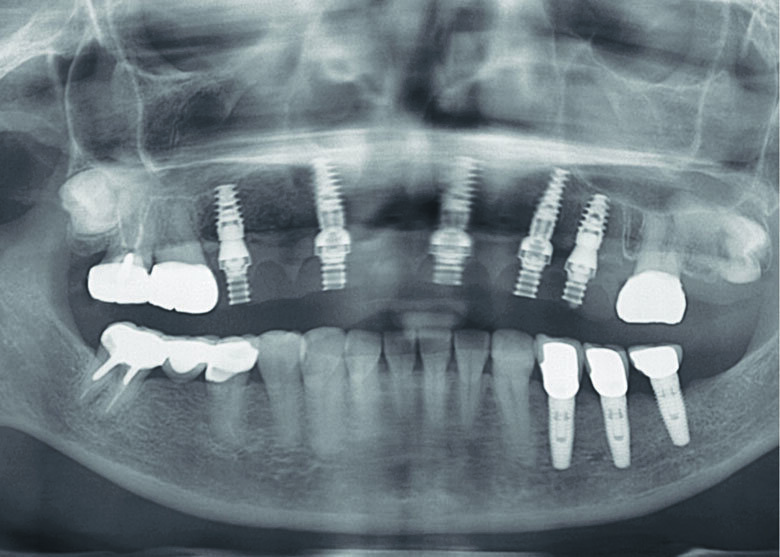

The initial clinical examination revealed a long-span Porcelain-Fused-to-Metal (PFM) FDPs of teeth 14-25 fixed with temporary cement since 2009 at private hospital (Fig 1,2). The patient had maxillary hard and soft tissue defects associated with alveolar ridge resorption and loss of lip support. Removable Acrylic Gingival Veneer (AGV, Fig 3.) was used to cover those FDPs in order to improve extra-oral soft tissue profile (Fig 4.). Without AGV, the patient has concave profile (Fig 5.). FDPs were removed to evaluate the existing abutments condition (Fig 6.). Abutment teeth 13,24,25 had first degree mobility. Panoramic XRAY (Fig 7.) revealed that tooth 13 had cast post and core with vertical root fracture. Tooth 25 was endodontically treated with a periapical lesion. After thorough diagnosis and analysis, the treatment plan was presented to the patient with the following phased treatment approach:

Fig 7. Pre-operative Panoramic XRAY

Fig 22. Post-operative panoramic XRAY

The existing provisional bridge was utilized for converting to a provisional screw-retained prosthesis. An immediate loading protocol was utilised2. Metal temporary abutments were connected on each implant. Provisional full arch bridge was perforated to match the position of the metal temporary abutments, placed in their correct position and OVD, relined with self-cure acrylic resin. All surfaces were fine-polished. A light-cure denture sealant (Palaseal, Kulzer) was applied on the intaglio surface. The provisional bridge was delivered to the patient’s mouth. (Figs. 23-27) Post-operative panoramic XRAY revealed that implants were placed according to the pre-operative planning (Fig. 22) Suture was removed after surgery 14 days. A final profile protheses3 will be fabricated after implant osseointegration.